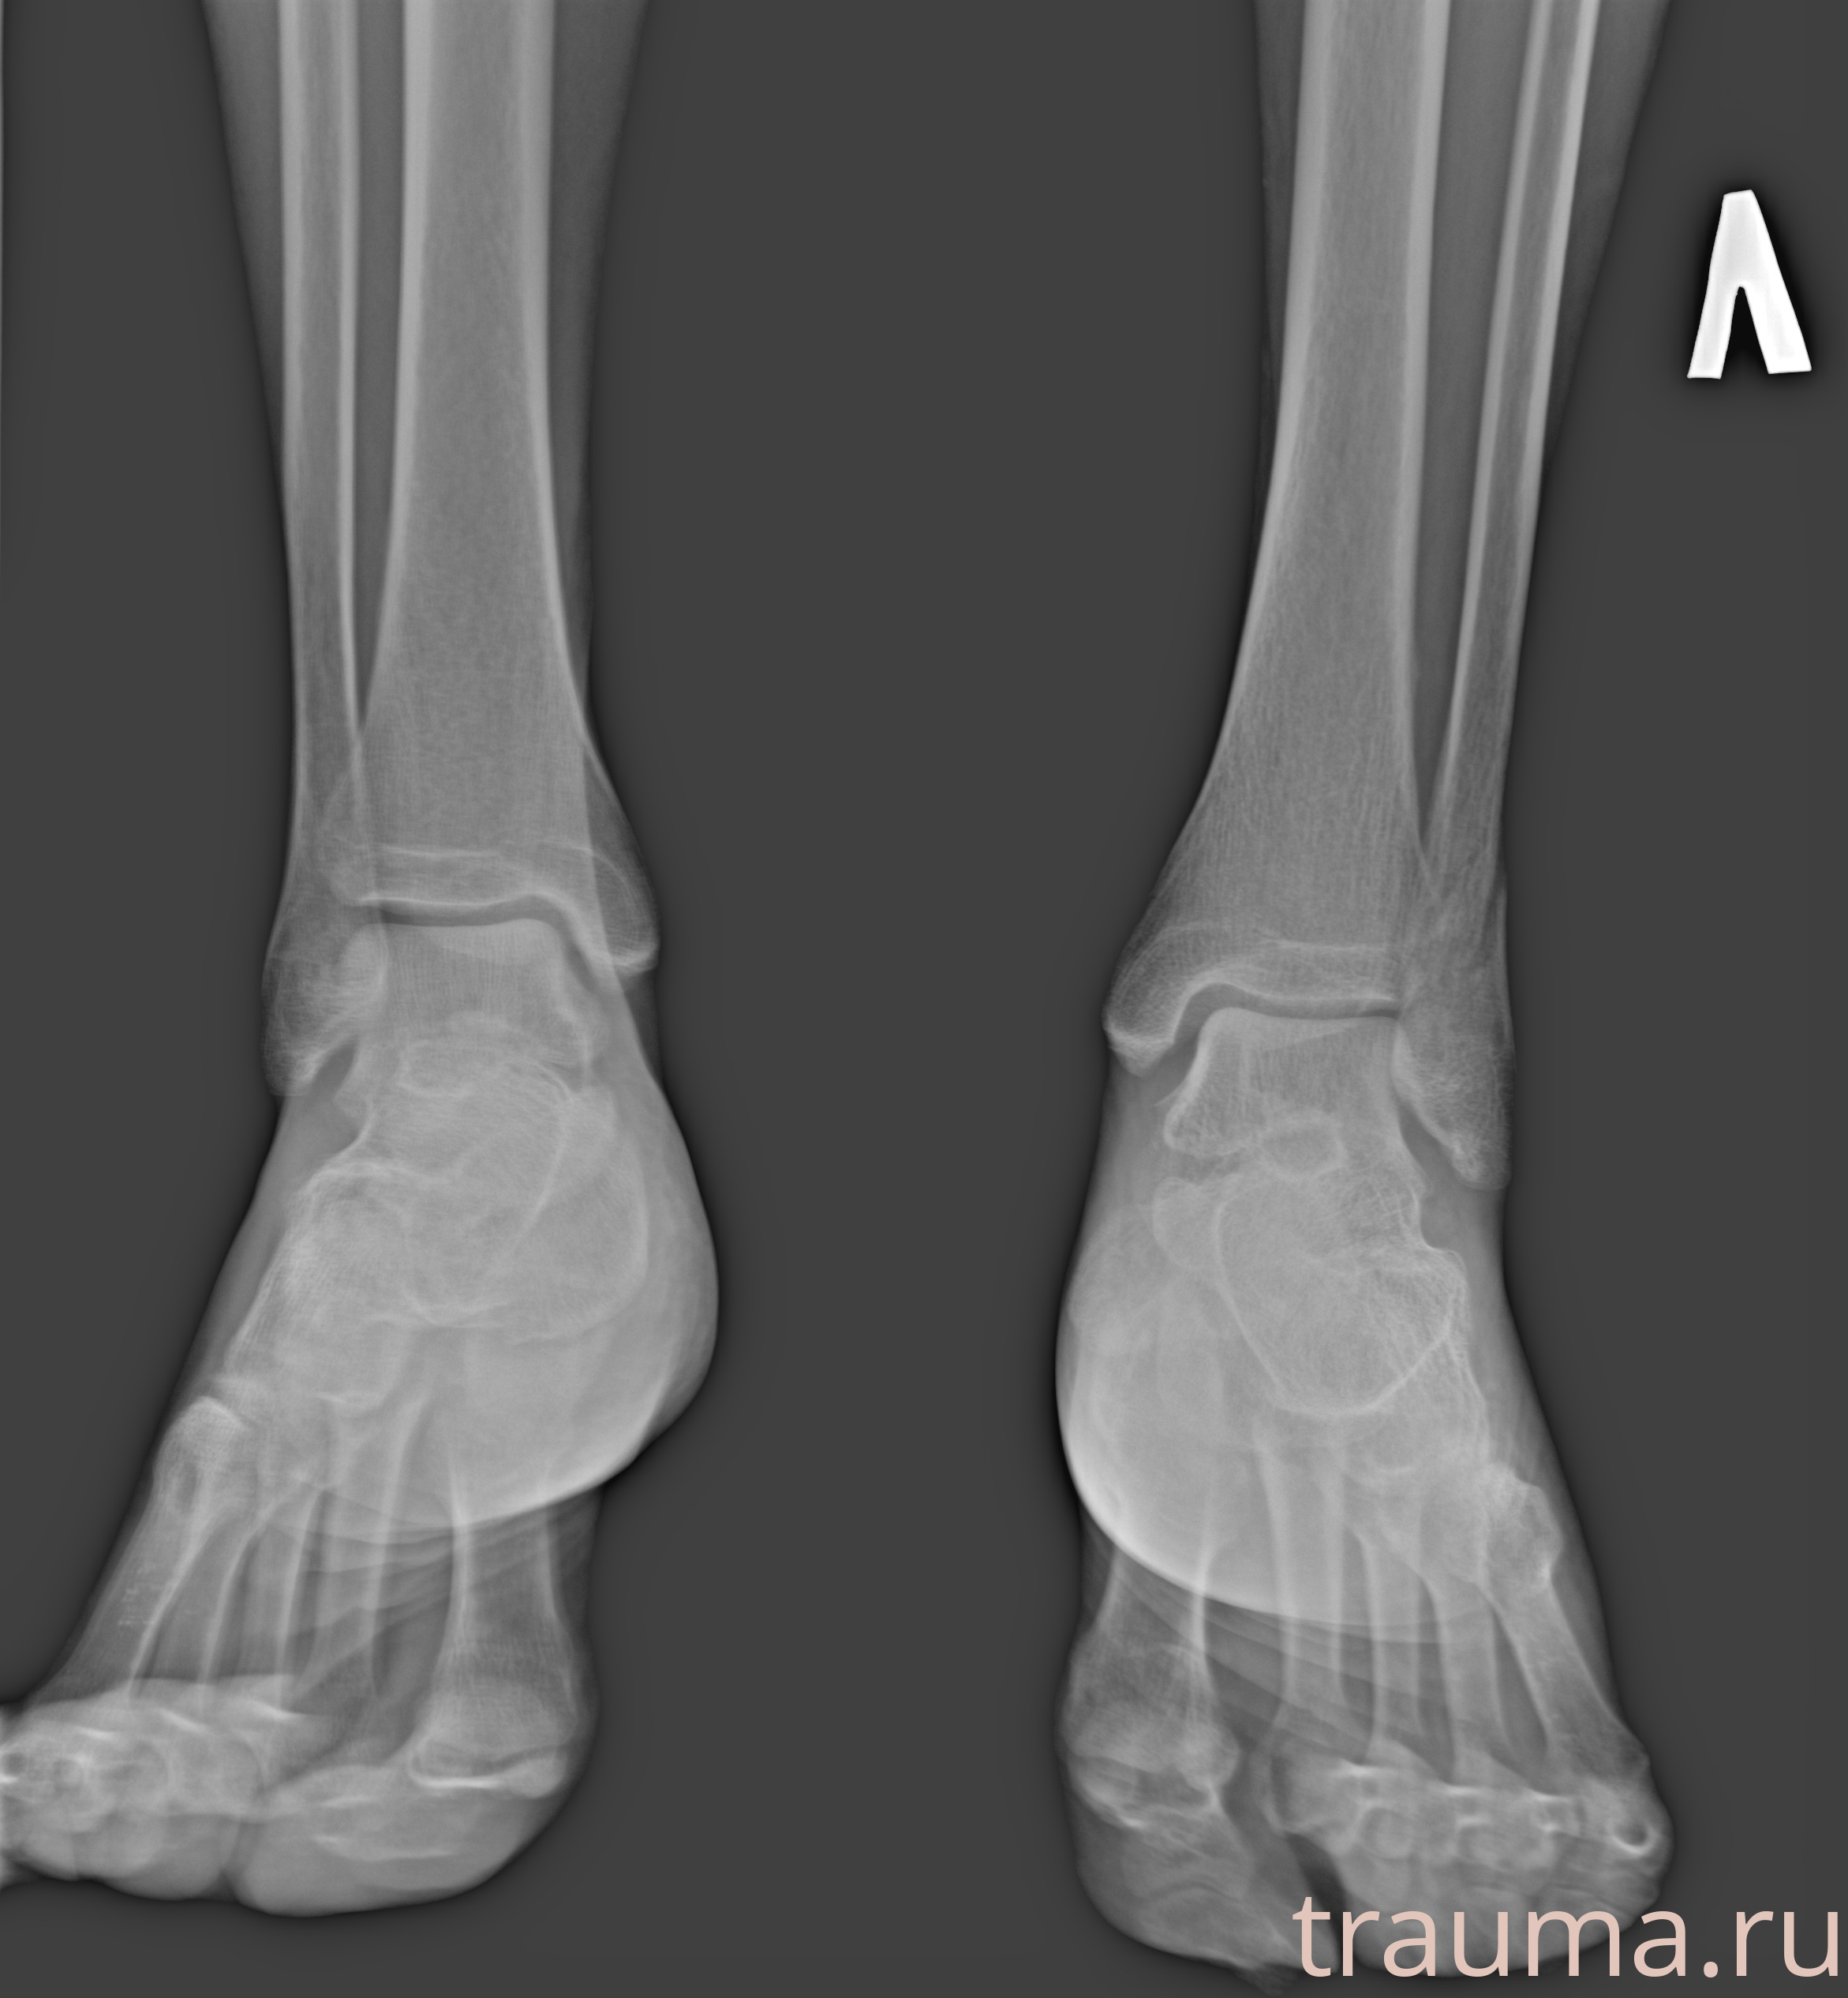

Рентгенограммы

Рентген на дому: по вашему адресу приезжает врач-рентгенолог, травматолог-ортопед с мобильным рентгеновским аппаратом, проводит диагностику травмы или заболевания, делает необходимые рентгенограммы, дает рекомендации по дальнейшему лечению. Получить качественные снимки в домашних условиях возможно благодаря уникальной методике, разработанной МосРентген Центром для института  Склифосовского

Яркость: 1   Контраст: 1   Инвертировать: 0 Увеличение: 1

Перетаскивайте мышь вверх/вниз для контраста, влево/право для яркости. Прокрутка колесом изменяет масштаб. Нажмите Сбросить для возврата к исходному изображению. При увеличении держите мышь в той области, которую хотите рассмотреть.